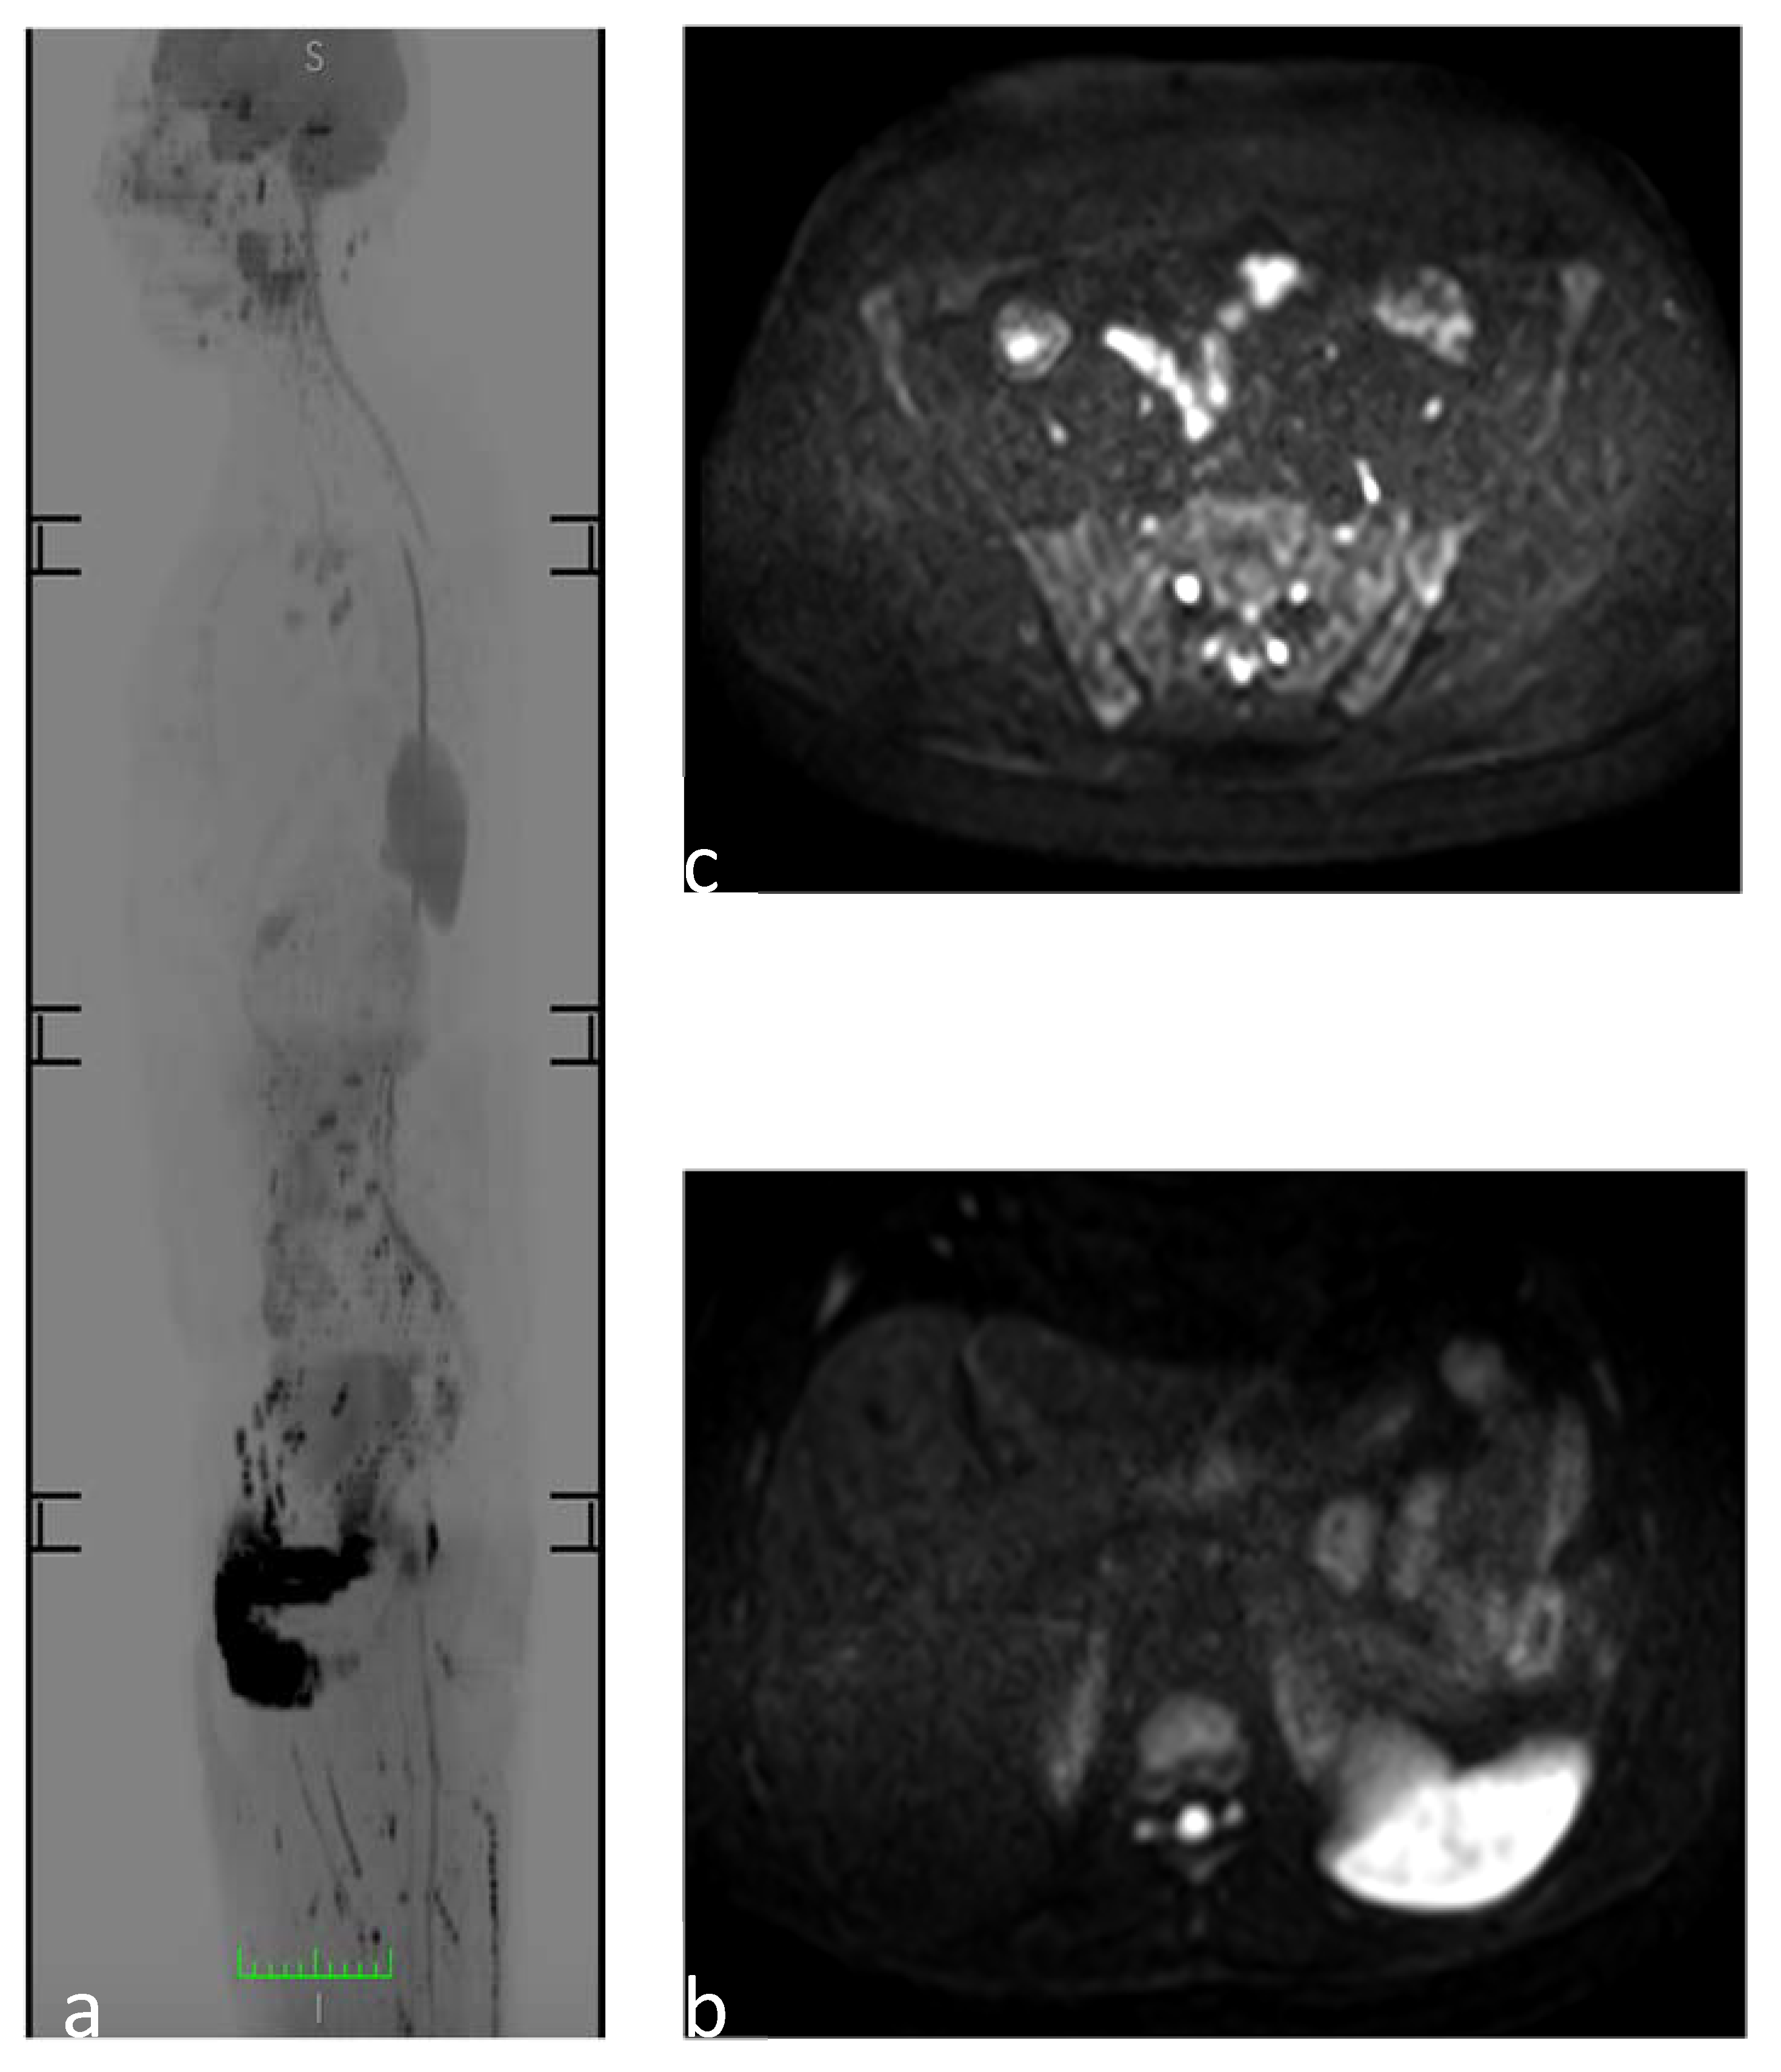

3.9. Avascular Multifocal Osteonecrosis (AVN)

3.10. Polyostotic Fibrous Dysplasia (PFD)